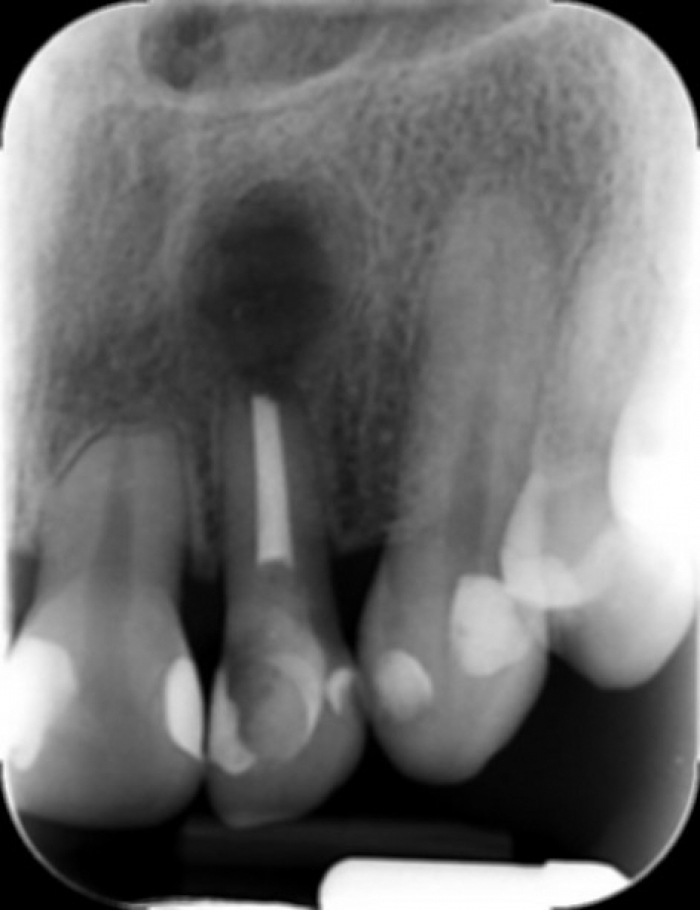

Raio x após curetagem da lesão e plastia apical do dente 22 - Clínica Cliniface

Raio x após curetagem da lesão e plastia apical do dente 22